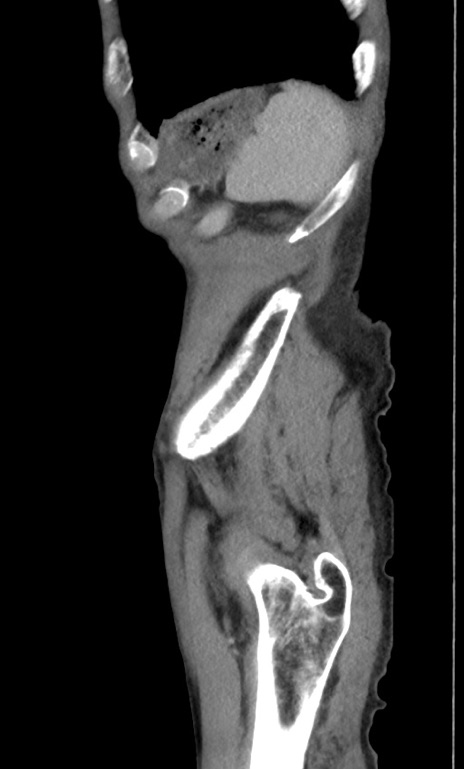

症例3(矢状断像)

【症例】 70歳代男性

【主訴】右鼠径部腫瘤、疼痛

【現病歴】本日朝より上記主訴あり、受診。

【既往歴】膀胱癌にて膀胱全摘、両側尿管皮膚瘻

【データ】WBC 5600、CRP 0.56